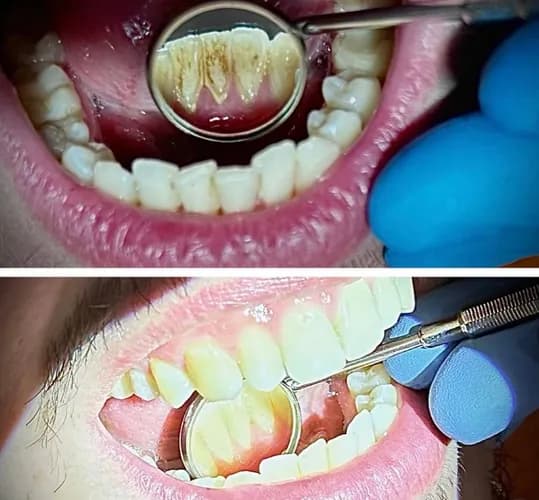

Професійна гігієна зубів у Варшаві